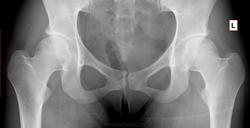

Динамика АНГБК

Спасибо, что с контролем. Показательно.

показательный законченный случай. спасибо.